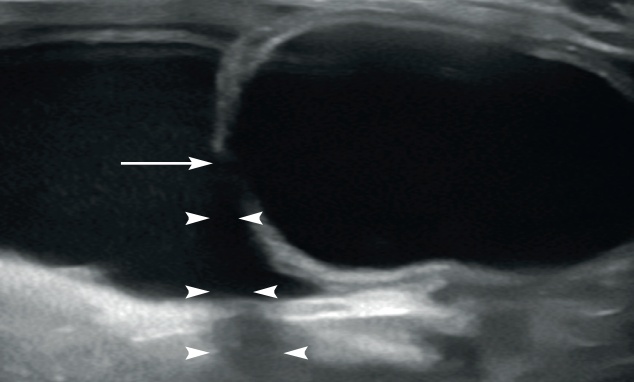

저에코성 혹은 무에코의 수질(medulla)을 확장된 신우로 혼동하지 않는 것이 중요합니다. 신우 확장은 보통 초음파 횡단면(transverse plane)에서 더 쉽게 보입니다. 신우 안의 액체는 심장 모양 또는 초승달 모양의 무에코성 부위로 보이며, 신장 능선(renal crest)을 감싸는 형태를 보입니다(그림 1).

신장을 배 측면(dorsal plane)으로 보면 신우 확장은 선형~타원형으로 보입니다. 확장이 점점 심해지면 신우는 둥근 모양을 나타냅니다(그림 2).